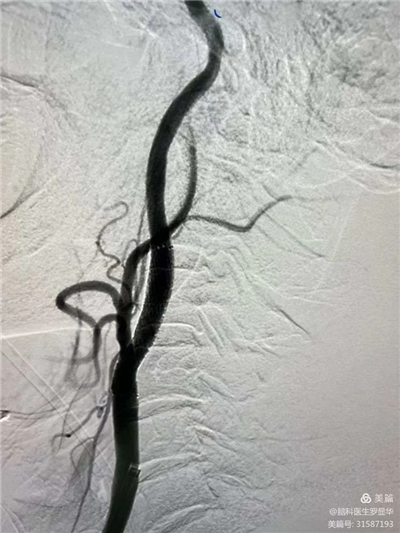

李東波副院長(zhǎng)團(tuán)隊(duì)正在為患者行頸動(dòng)脈支架植入術(shù)

手術(shù)過(guò)程:指引導(dǎo)管到位

手術(shù)過(guò)程:球囊擴(kuò)張后,protege支架到位

術(shù)后造影示狹窄解除